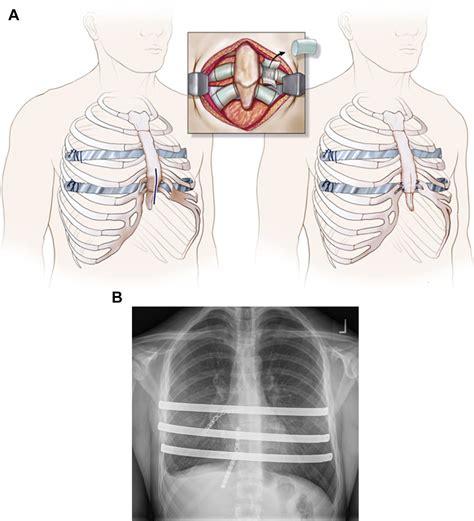

The Nuss Surgery Pectus Excavatum procedure, also known as the Nuss procedure, is a minimally invasive surgical technique developed by Dr. Donald Nuss. This procedure involves the insertion of a concave metal bar behind the sternum to gradually push it outward, correcting the concave shape of the chest. The surgery is typically performed on adolescents and young adults, as the chest is still growing and more malleable.

The Nuss Surgery Procedure

The Nuss Surgery Pectus Excavatum procedure is generally performed under general anesthesia. The steps involved in the surgery are as follows:

• Incision: A small incision is made on the side of the chest.

• Bar Insertion: A curved metal bar is inserted behind the sternum through the incision.

• Bar Flipping: The bar is then flipped, so the convex side faces the sternum, gradually pushing it outward.

• Closure: The incision is closed with sutures, and the bar is secured in place.

The entire procedure typically takes about one to two hours. Patients usually stay in the hospital for a few days post-surgery for monitoring and pain management.